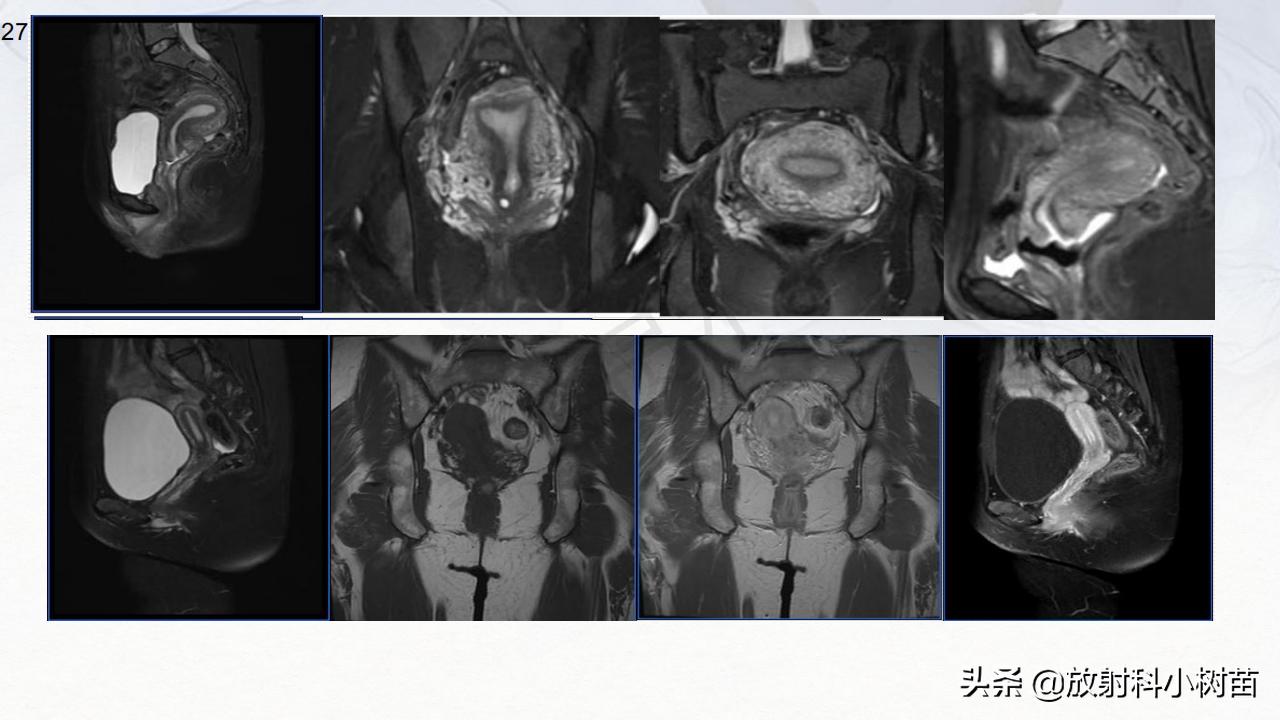

内胚窦瘤:是一种胚胎外结构卵黄囊发生的高度恶性的生殖细胞肿瘤,是小儿生殖细胞来源恶性肿瘤中最常见的肿瘤。4月-14岁;囊实性为主,呈明显不规则强化,AFP明显升高。

颗粒细胞瘤分化差异大,偏良性至恶性,影像学表现也多样,实性-囊实性,典型征象为-实性肿块内多发囊变;是最常见的雌性激素作用的卵巢肿瘤,故常伴有子宫内膜增生,子宫增大,假性性早熟。好发于10-30岁,盆腔较大实性肿块,境界清楚,有包膜,轻中度强化,内可有肿瘤坏死,包块生长快,病程短,但并不是很恶性的表现,也无明显腹水,一般情况较好。青少年盆腔巨大实性肿块,一般情况好。